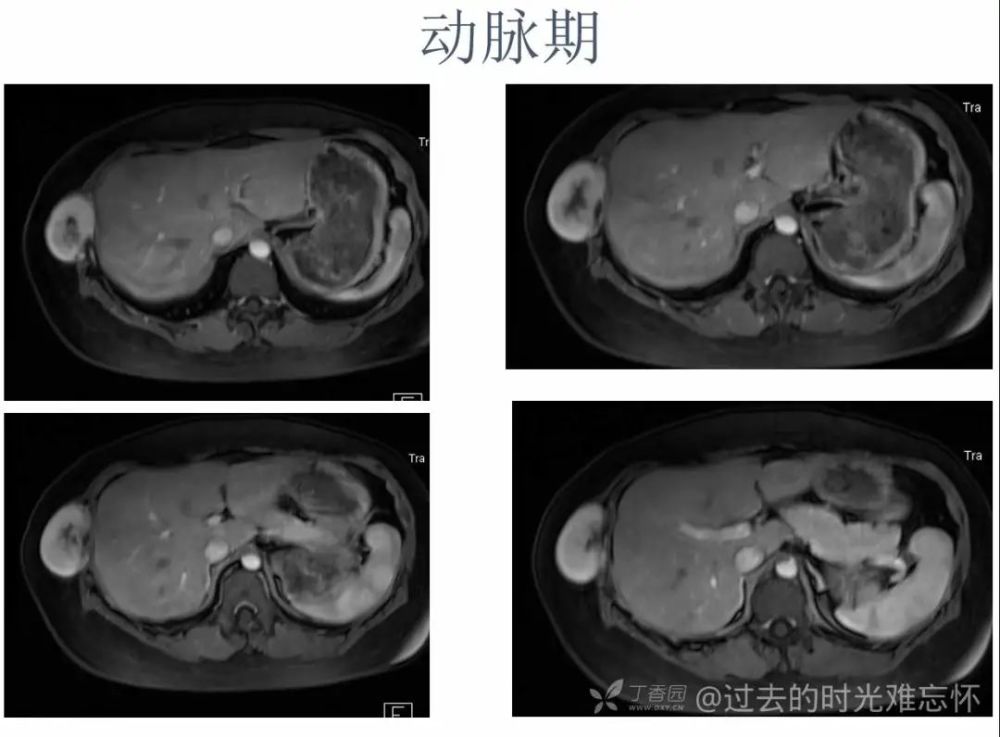

女,22 岁。右下侧胸壁疼痛、不适 10 年,近 3 年发现右侧腋中线近肋弓处肿块。体检:局部皮肤无红肿,肿块质中等偏硬,活动度欠佳,压痛( + ),无血管杂音。超声描述「低回声包块」。化验室指标无异常。